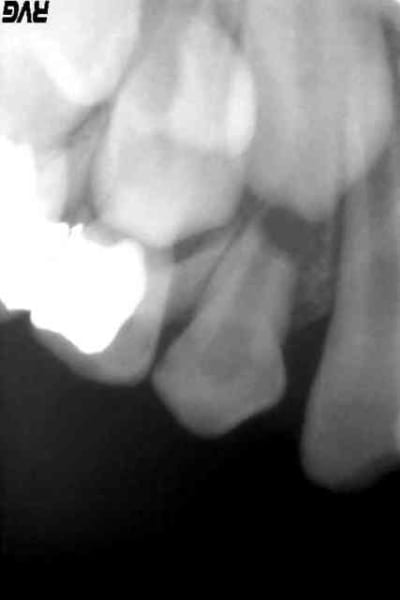

En PJ : les radios le jour de la cellulite, avec la 53 en place, et la radio de la 22 par comparaison. La première est la radio d'aujourd'hui, la 13 étant un peu descendue.

je vois une belle lésion autour de l'apex de la 12.

pas vous?

L'image à l'apex de la 12 n'est pas évidente non plus.

je suis très intriguée par les radios initiales du cas de traumato.

Je voudrais juste parler des radios de 12 et de 22.

Sur les 2 l'apex est largement ouvert, ce qui est normal.

Par contre sur la 12 il y a une image radio claire tout autour de l'apex.

Cette image est excessivement volumineuse, elle remonte à plus de la moitié de la racine.!

Suis je la seule à la voir, ou la voyez vous?

(Attendre, attendre oui, la destruction osseuse peut continuer sans bruit , jusqu'à la perte de la dent ou alors on tentera une apexification avec un pronostic très très réservé)

La présence d'une image apicale pour la 12 n'est pas si évidente que cela. La continuité de la corticale est bien visible sauf en regard de la 13, ce qui se retrouve aussi avec la 22-23. Les deux radios ne sont malheureusement pas exposées pareil donc difficile de comparer la densité osseuse.

je ne trouve pas non plus la corticale au niveau de la 12 soit continue, sur les 2 radios de la 12.

bonjour,

Je suis d'accord avec vous MAUVE , il existe une image périapical.alors, s'abstenir ou agir! je vote pour la deuxième,parce que l'os est entrain de se résorber et c'est ce que montre la radio et surtout dans ce cas le patient ne semble pas être très motivé and you can't always 'see'!